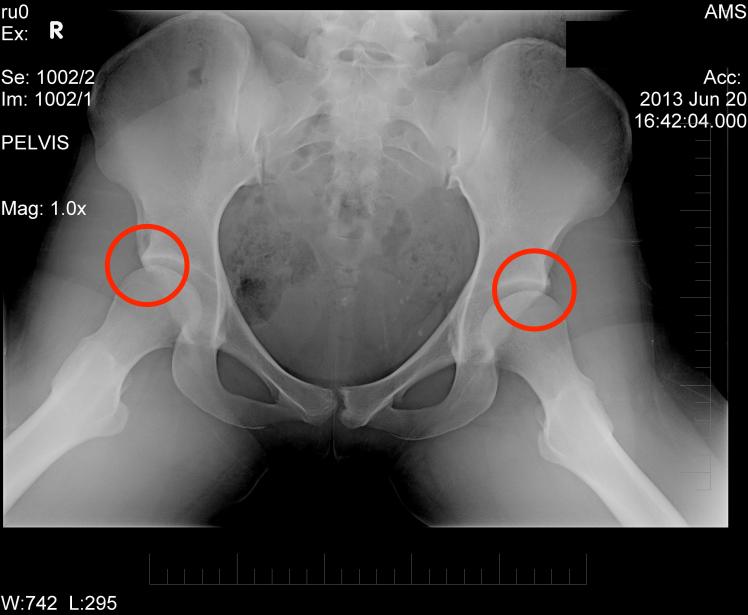

I was diagnosed with bilateral hip dysplasia at the age of 18. For those of you unfamiliar with this condition, hip dysplasia describes a hip that, for one reason or another, has not formed properly. In my case, this meant shallowness of the hip socket (the acetabular), anteversion (the ball faces the wrong direction), and impingements and growths on both sections of the joint. This condition affects thousands of people around the world, and if left untreated can lead to severely reduced mobility, torn labrums (the cartilage that fills your hip joint), osteoarthritis, osteotomies or hip replacements.